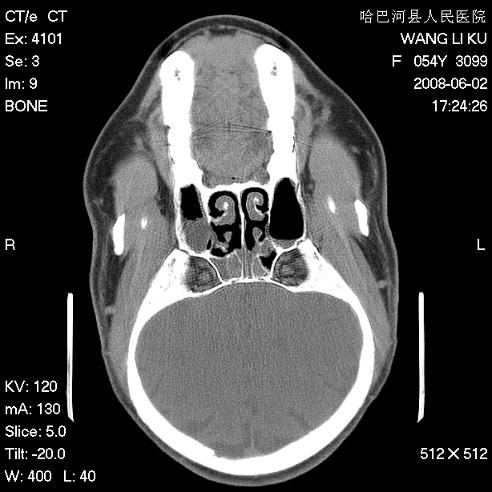

标题: CT13803:反复性鼻塞、流涕一年余 [打印本页]

标题: CT13803:反复性鼻塞、流涕一年余

副鼻窦炎,右上额窦积脓。左眼肌锥内见致密影,视神經受压

1.全组副鼻窦炎2.双侧上颌窦积液

1)全副鼻窦炎(左侧上颌窦黏膜下囊肿或息肉)。2)左眼眶肌锥内不规则小结节状软组织密度影;考虑为小血管瘤可能。建议行ct增强扫描检查。

全组副鼻窦炎,左侧肌锥内不规则形软组织肿块影,与眼外肌密度相当,左侧视神经受压,肿块与视神经及眼外肌分界清晰,眼外肌无增粗,眶壁无破坏,球后脂肪间隙不模糊,考虑良性改变,小血管瘤或神经源性肿瘤可能,建议增强扫描。

谢谢,增强扫描做了,眶内病灶与海绵窦同步明显强化,血管瘤